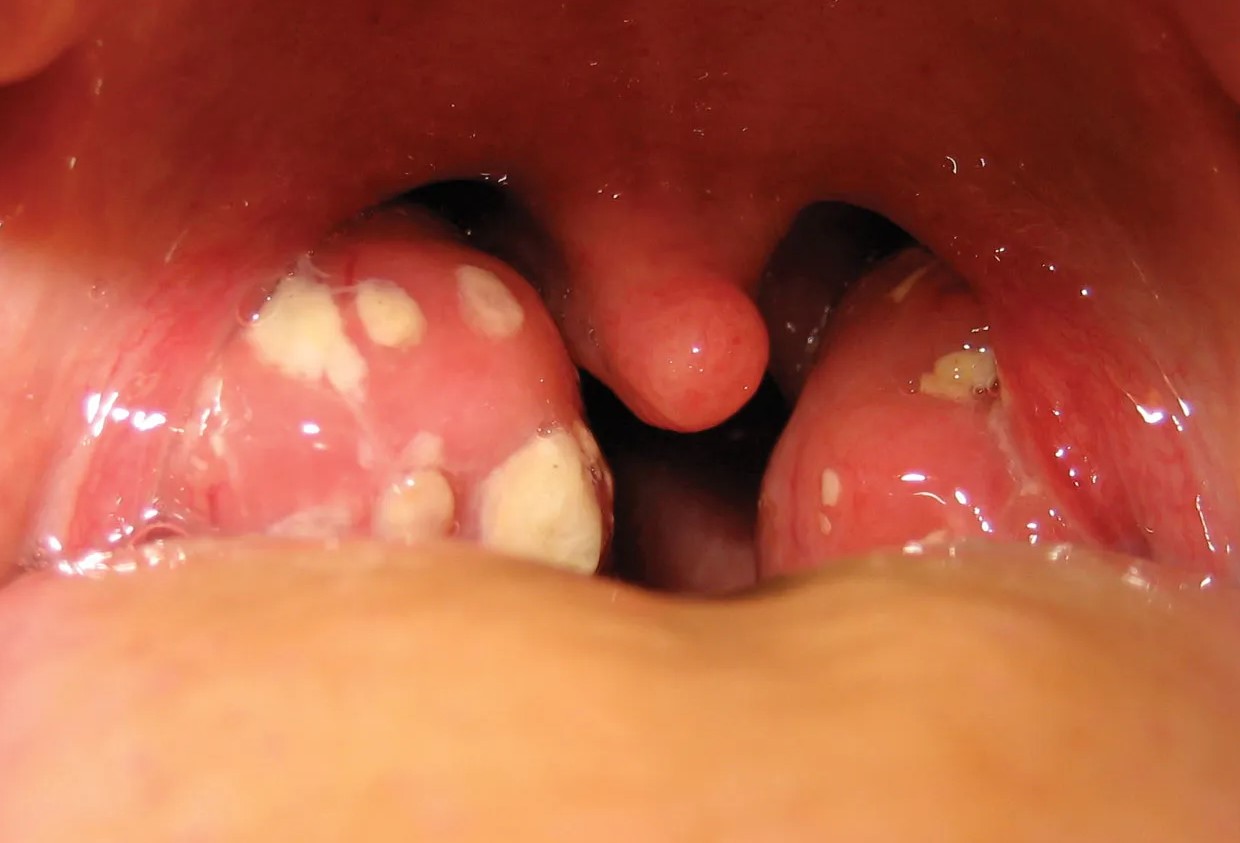

발열과 통증이 심하다면 타이레놀과 같은 일반 의약품을 복용해 증상을 완화할 수 있습니다. 단, 복용 전 사용설명서를 꼭 확인하세요.7. 필요시 병원 진료

편도에 하얀 고름이 보이거나 고열이 3일 이상 지속될 경우, 세균성 감염일 수 있으므로 항생제가 필요할 수 있습니다. 반드시 병원에 방문해 정확한 진단을 받으세요.8. 꿀물이나 생강차 활용